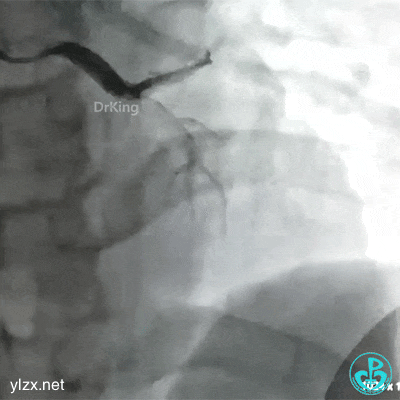

急诊冠状动脉造影

右冠脉光滑无狭窄,前降支2级血流,近端可见巨大血栓。